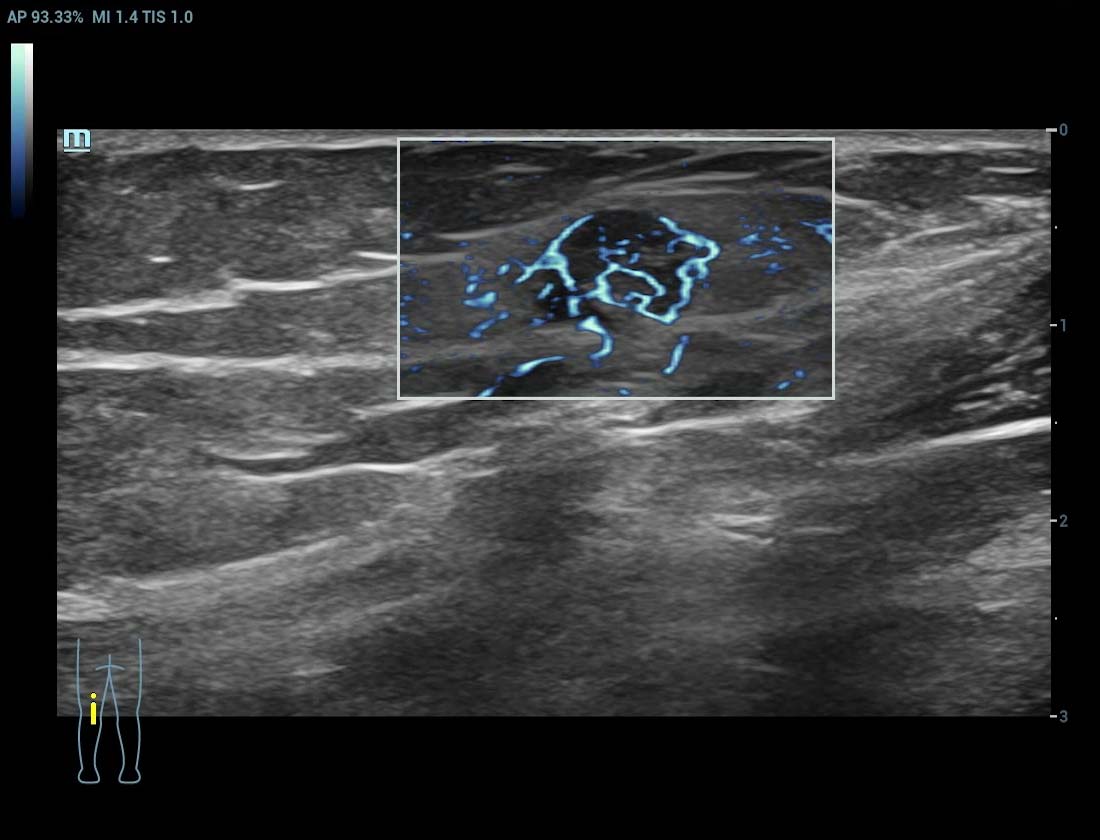

Ultra-Micro-angiografie (UMA)

UMA verbetert het diagnostische vertrouwen door de zichtbaarheid van de bloedstromen uit te breiden tot op het kleinste vaatniveau, met een superieure gevoeligheid en resolutie van de bloedstroom.

sUMA Schildklierkanker

Lymfeklieren sUMA